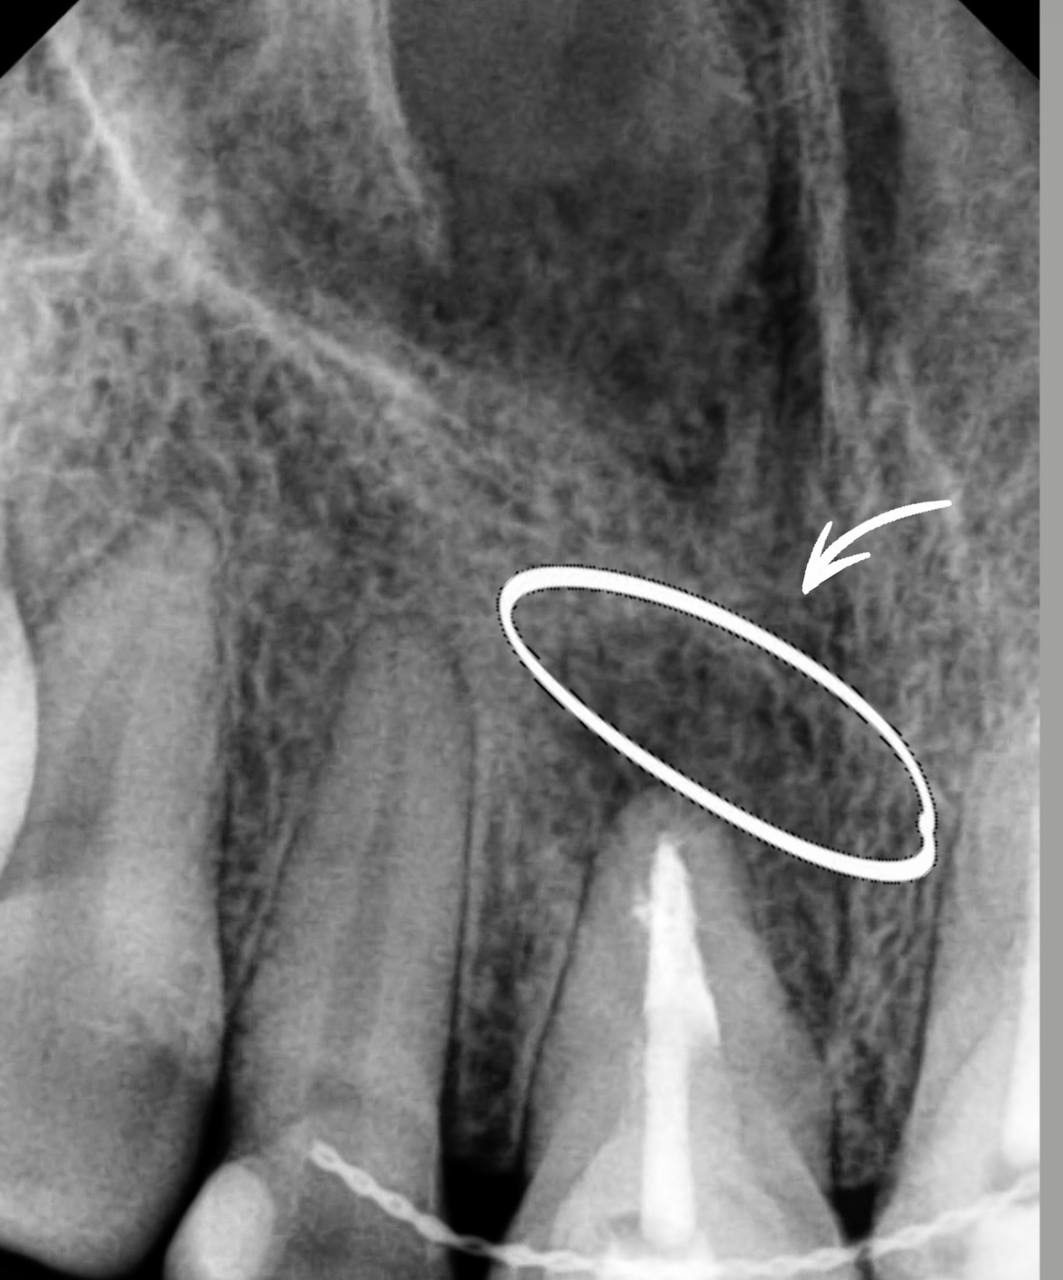

Эндодонтия